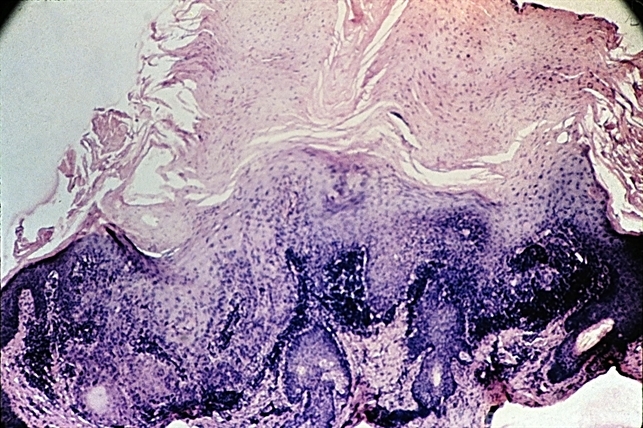

- senile keratosis, hyperkeratinization, dermal infiltrate

- Senile keratosis has marked hyperkeratinization with columns of para keratosis and dermal infiltrate.